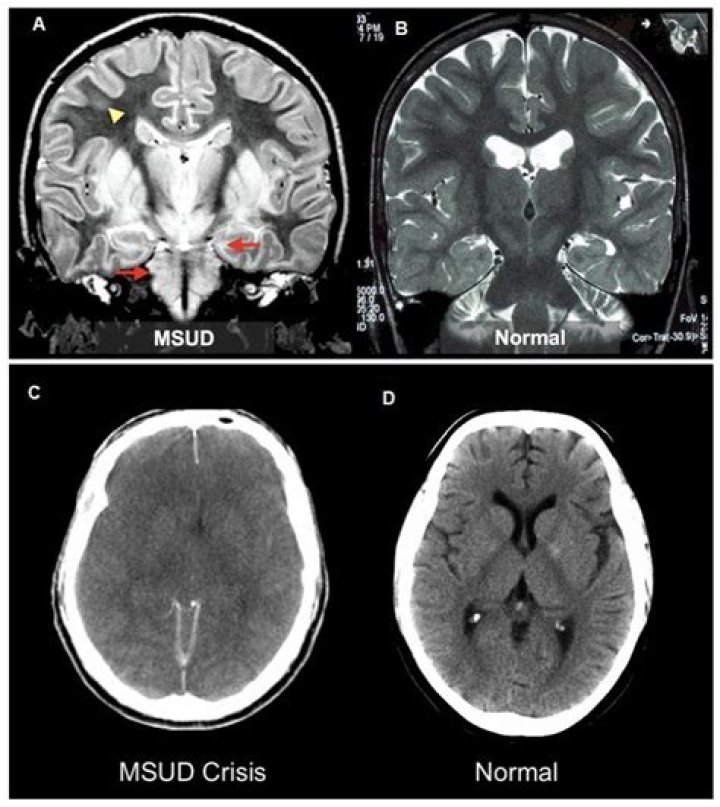

If untreated, life-threatening coma or respiratory failure could occur within 7 to 10 days and most will die within several months. Upon any lapse of treatment, classic MSUD can cause brain damage.